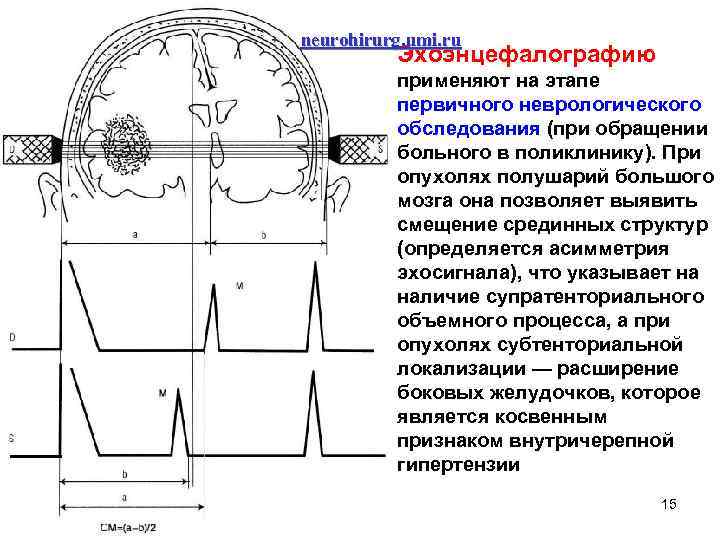

neurohirurg. umi. ru Эхоэнцефалографию применяют на этапе первичного неврологического обследования (при обращении больного в поликлинику). При опухолях полушарий большого мозга она позволяет выявить смещение срединных структур (определяется асимметрия эхосигнала), что указывает на наличие супратенториального объемного процесса, а при опухолях субтенториальной локализации — расширение боковых желудочков, которое является косвенным признаком внутричерепной гипертензии 15